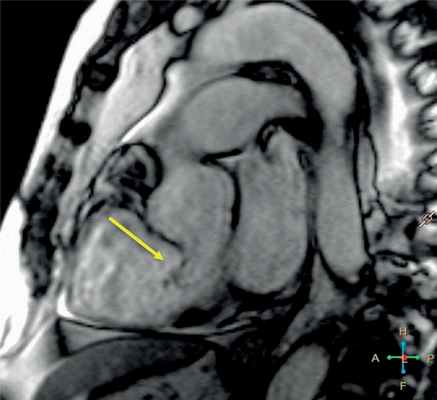

Рис. 3. Магнитно-резонансная томограмма сердца пациента И., наклонная ось.

Стрелка указывает на некоронарный синус Вальсальвы, где определяется дефект, величина дефекта 7 мм.